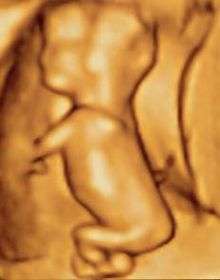

Fetal stage is from 9 weeks to term. During this period of time, the embryo develops rapidly and becomes a fetus. Pregnancy becomes visible at this stage.[1]

Fetus at 38 weeks after fertilization[3]

- ^ 3D Pregnancy (Image from gestational age of 40 weeks). Retrieved 13 December 2010. A rotatable 3D version of this photo is available here, and a sketch is available here.